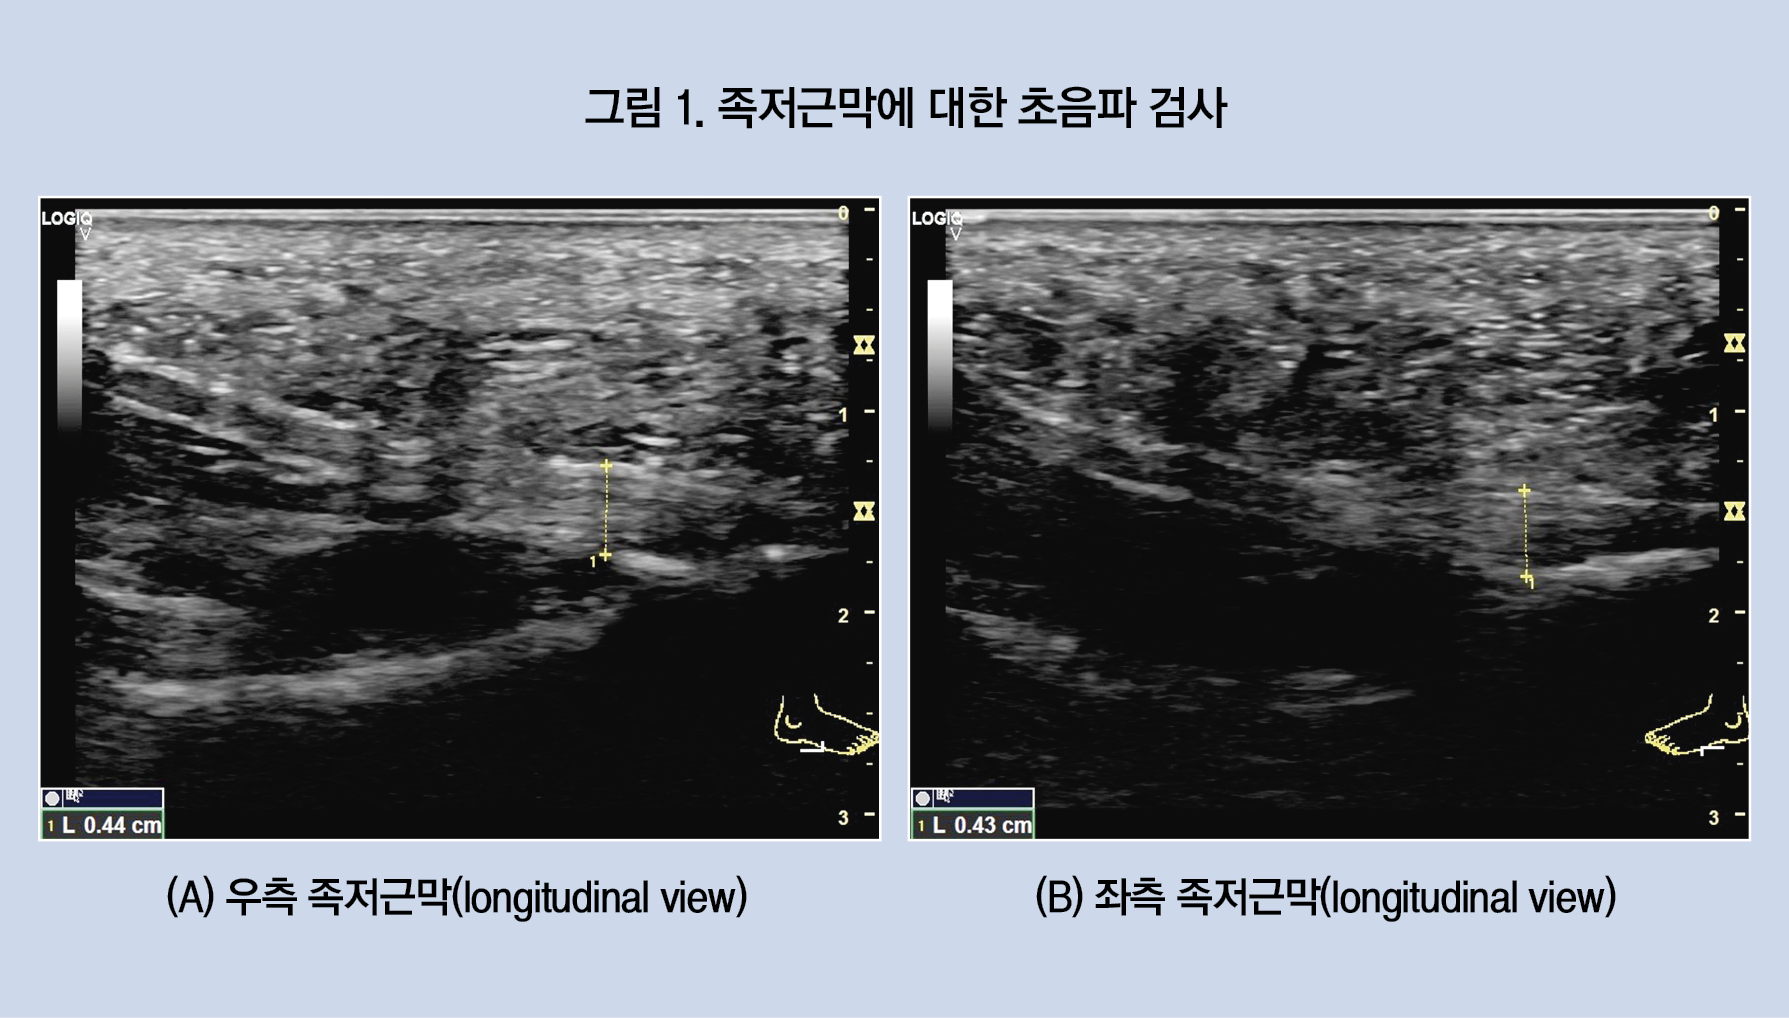

환자는 족저근막염 진단 과정에서 족저근막에 대한 초음파 검사를 시행한 적이 없다고 했다. 이에 족저근막 평가를 위해 초음파 검사를 시행했다. 검사상 양측 족저근막의 두께가 약간 두꺼워져 있음(우측 0.44 cm, 좌측 0.43 cm)이 관찰됐다(그림 1).